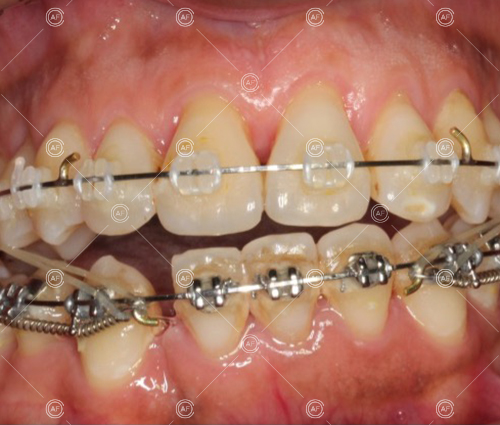

This patient (MH) began her active orthodontic treatment in October 2019 at almost 13 years old. She was unhappy with the appearance of her upper and lower teeth, and especially concerned about the unsightly nature of the high and buccally positioned upper left canine.

about this case…MH presented with class 1 incisors on the class 1 skeletal base with a slightly increased vertical proportion. She had severe crowding in the upper arch and moderate crowding in the lower. Due to the crowding in the lower arch, the lower centre line was off to the left by 2mm.

Buccal segments were essentially class 1 on the right hand side and a full unit class 2 on the left. This is due to buccal exclusion of the upper left 3 and mesial drift of the upper buccal segment.